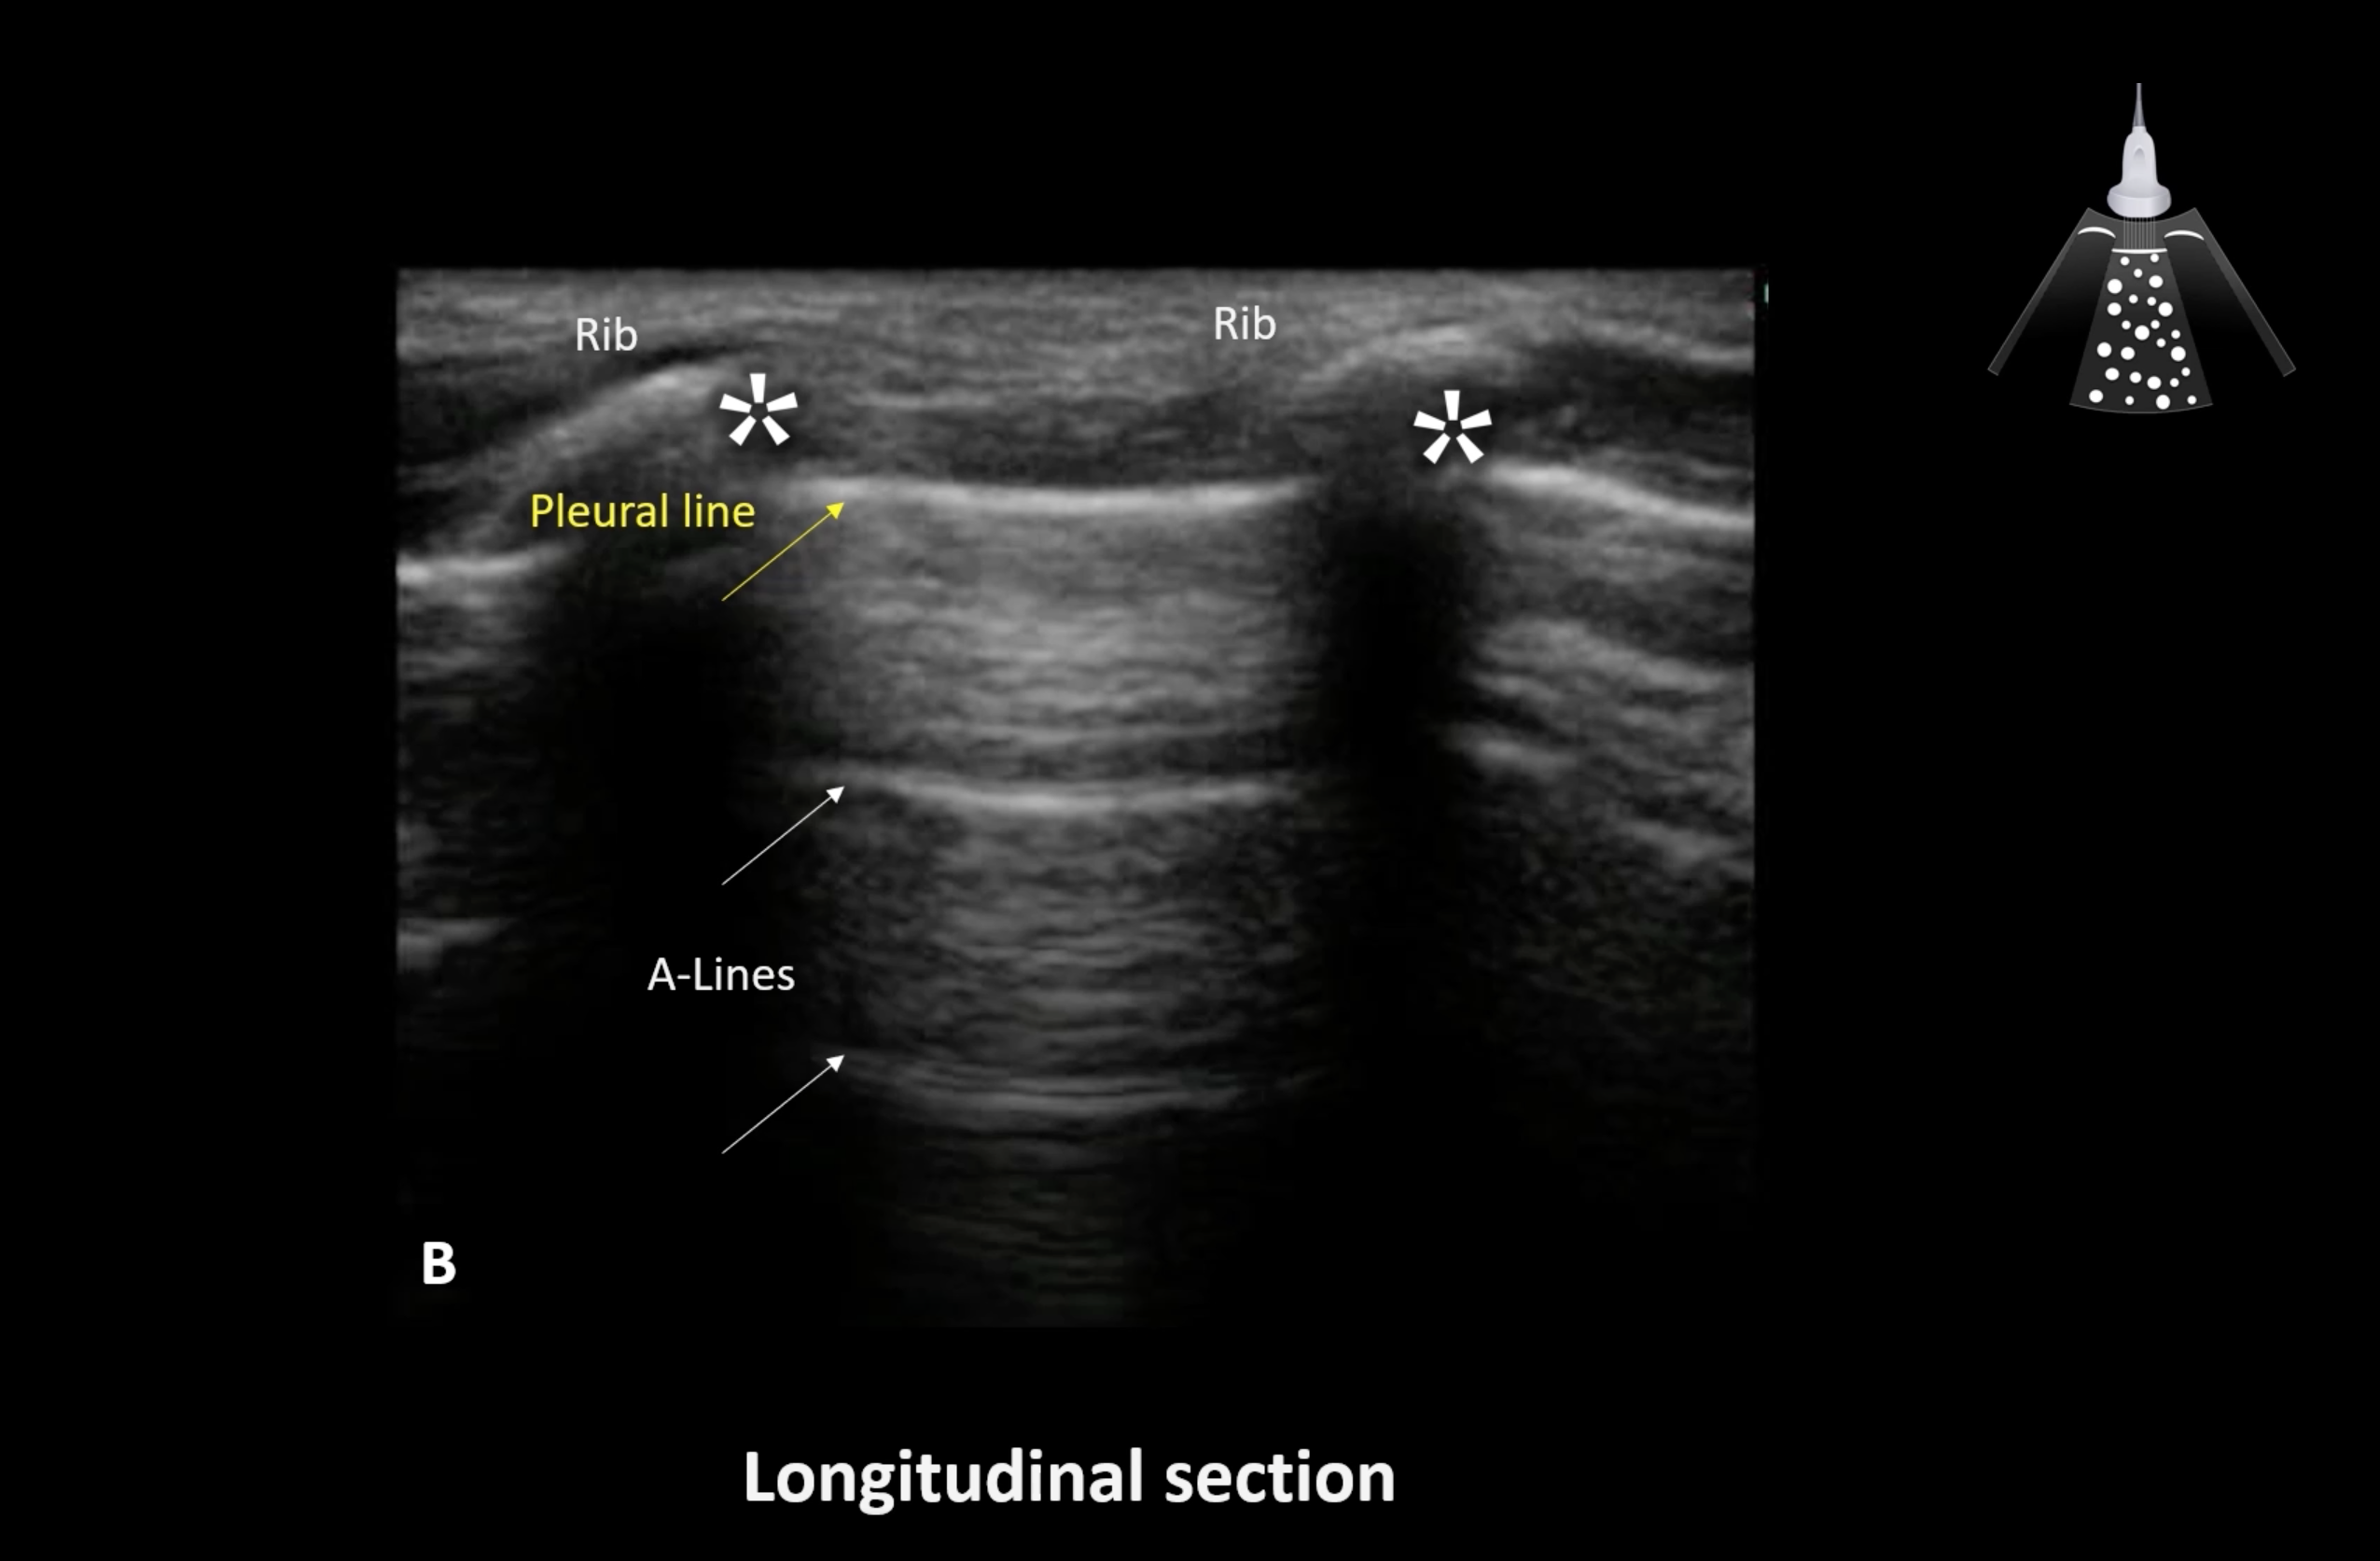

Covid 19 and Lung Ultrasound

These are the latest Covid 19 and Lung Ultrasound images from around the world.